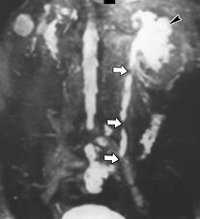

Диагноз стриктуры мочеточника устанавливает врач-уролог по результатам УЗИ почек, УЗДГ сосудов, рентгеноконтрастного обследования, КТ почек и МРТ. Проведение трехмерной УЗ-ангиографии с диуретической нагрузкой позволяет одновременно увидеть расширенный отдел мочеточника выше стриктуры и оценить сосуды почек.

Рентгенконтрастная урография (экскреторная, инфузионная, ретроградная) дает возможность визуализировать ткани почек и мочевыводящие пути, определить сужение мочеточников, протяженность стриктур, оценить снижение выделительной способности почек. В сложных случаях применяют КТ или МРТ, дополнительно выявляющие заболевания смежных органов и тканей, оказывающих влияние на почки и мочеточники.

КТ-урография. Резкое расширение чашечек и лоханки левой почки (красная стрелка), отсутствие контрастирования суженного левого мочеточника (синяя стрелка).